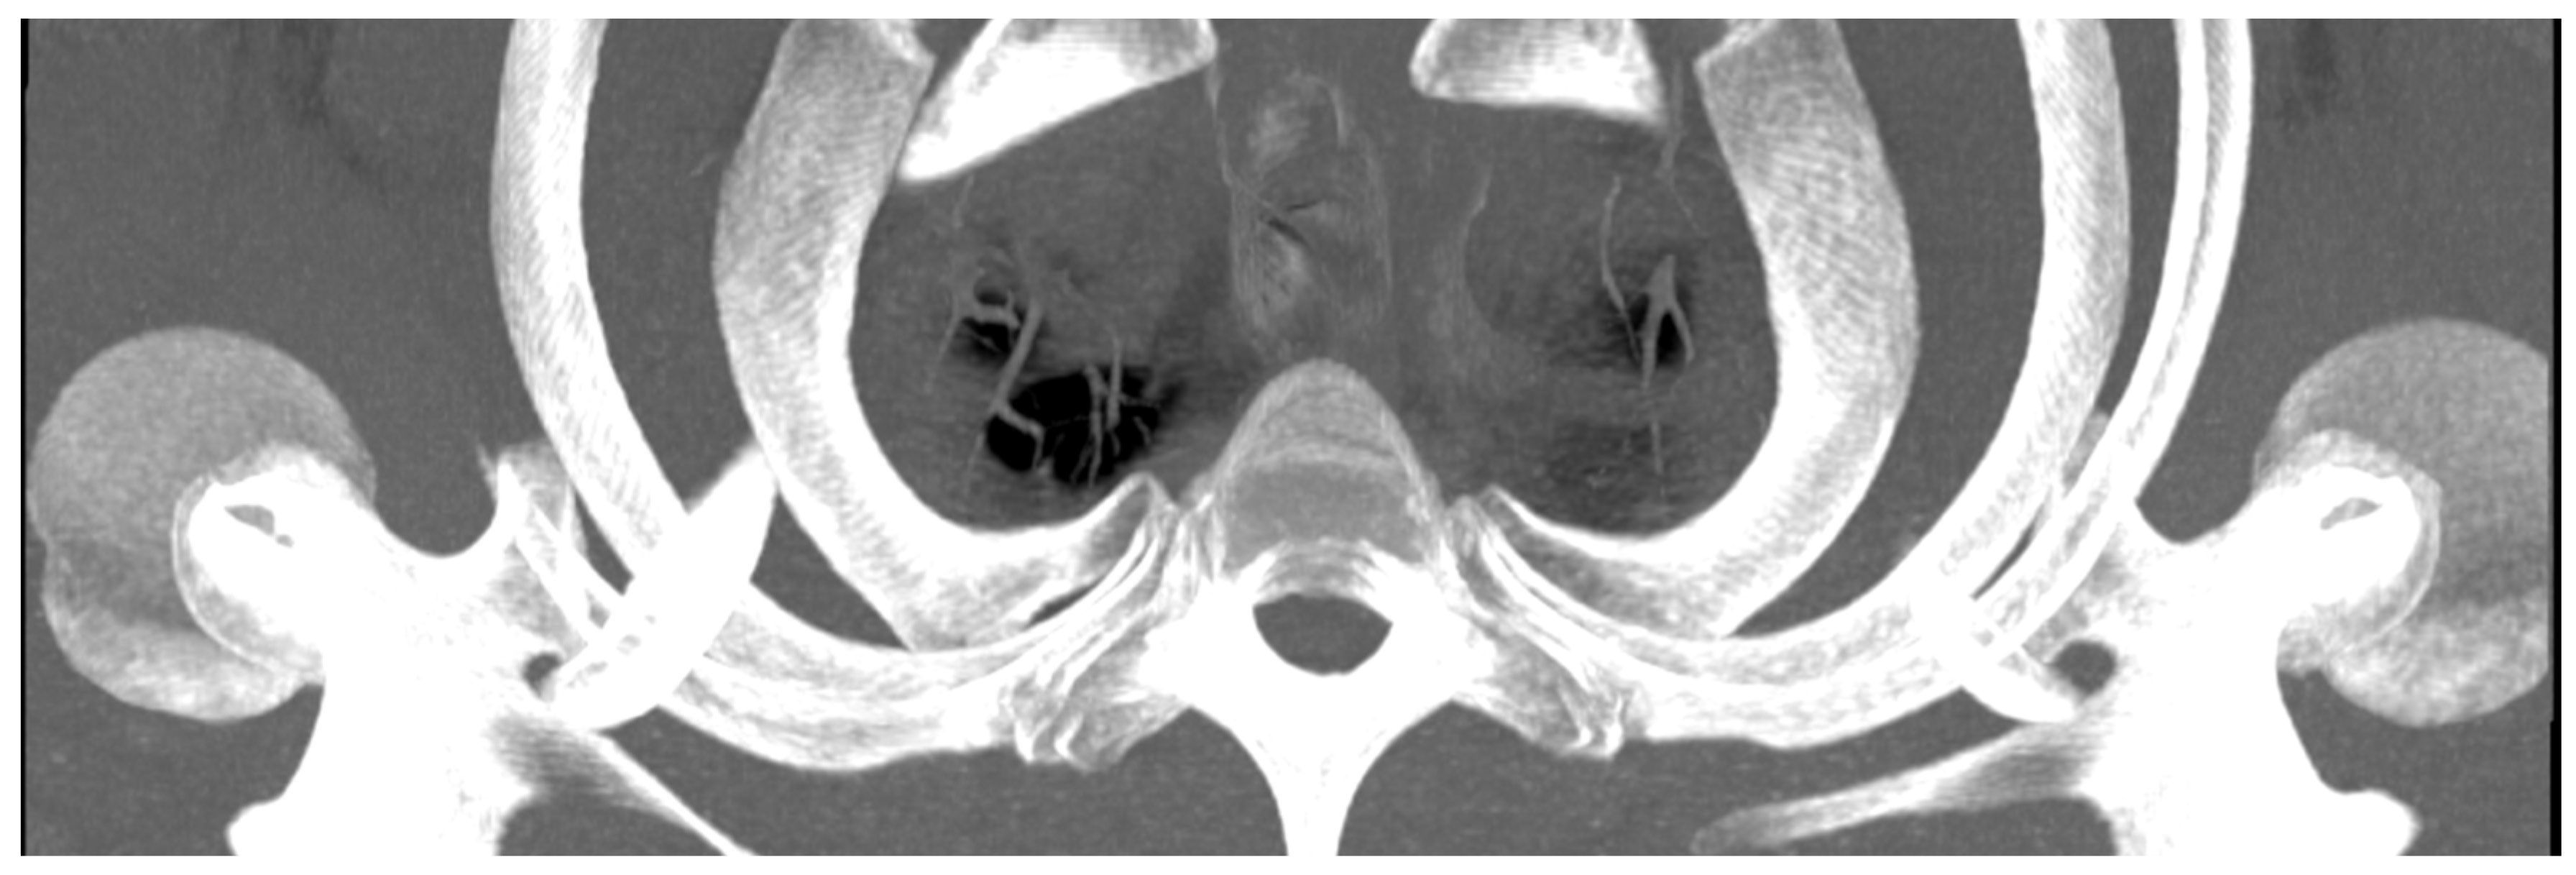

- Lassner, F.; Becker, M.; Prescher, A. Relevance of Costovertebral Exarticulation of the First Rib in Neurogenic Thoracic Outlet Syndrome: A Retrospective Clinical Study. J. Pers. Med. 2023, 13, 144. [Google Scholar] [CrossRef] [PubMed]